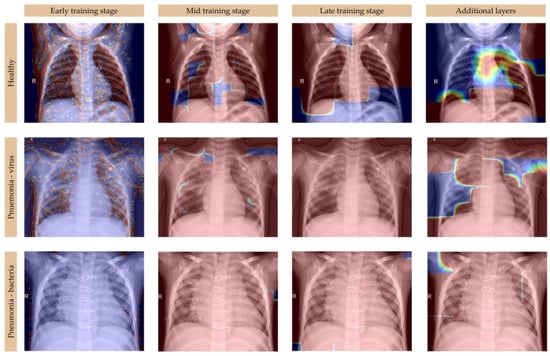

The consistent performance of MobileNetV2 with Approach 2 across training and validation metrics, coupled with its rapid convergence and stability, made it a suitable choice for detailed interpretability analysis using Grad-CAM, as presented in Figure 7. Its ability to generalize well, with minimal overfitting, underscores the importance of selecting models that balance performance, efficiency, and interpretability, particularly in medical image classification tasks, where false positives and false negatives can have significant clinical implications [,].

Figure 7.

Grad-CAM visualizations of MobileNetV2 with Approach 2 across training stages for the classification of healthy lungs, viral pneumonia, and bacterial pneumonia.

The integration of multi-scale convolutions with Mish activation in MobileNetV2 significantly improves heatmap-based lung disease detection by refining feature extraction across multiple spatial resolutions. This architectural enhancement enables the model to simultaneously capture fine-grained abnormalities, such as the diffuse opacities characteristic of viral pneumonia, and larger consolidations typical of bacterial infections. The multi-scale approach effectively suppresses false activations in non-pathological regions, maintaining precise focus on diagnostically relevant areas throughout the training process [,]. During the initial training phases, the multi-scale architecture mitigates scattered attention patterns by promoting more meaningful feature extraction. As training progresses to intermediate stages, it enhances consistency in activation patterns across diverse lung pathologies. In the final training stages, this approach produces sharply defined heatmaps, while preserving sensitivity to subtle pathological indicators that might otherwise be overlooked. The Mish activation function offers superior gradient flow and feature diversity compared to those of conventional ReLU activation [,]. Its smooth, non-monotonic characteristics address several limitations of traditional activation functions. Specifically, Mish prevents vanishing gradients during backpropagation while maintaining richer feature representations. This property proves particularly valuable in medical image analysis, where subtle pathological patterns require precise detection []. In early training iterations, Mish activation helps avoid suboptimal initialization traps that can hinder model convergence. During the intermediate training phases, it strengthens the mid-level feature extraction capabilities. In the final training stages, Mish activation yields more confident and precise spatial activations in the generated heatmaps. The combined implementation of multi-scale convolutions and Mish activation provides multiple synergistic benefits. First, it produces heatmaps with superior pathological localization. Second, it enhances classification accuracy for distinguishing between viral and bacterial pneumonia manifestations. Third, it significantly reduces activation noise in healthy tissue regions. Fourth, it accelerates model convergence, potentially enabling early stopping strategies, without compromising diagnostic performance. This optimized architecture demonstrates particular value in regards to clinical decision support systems, where reliable detection of pulmonary abnormalities must be maintained across diverse imaging conditions and acquisition protocols. The improved interpretability of the resulting heatmaps provides clinicians with more trustworthy visual explanations of the model’s diagnostic reasoning process.